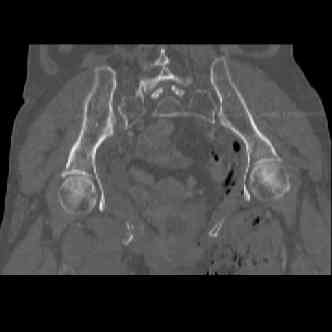

attached are several CT cuts. please let me know if you need more. the CT is pre-pelvic ex-fix placement.

Имя     : image003.jpg